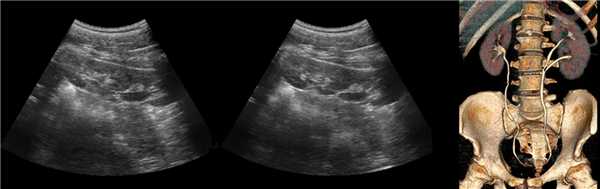

(Левый) Продольный ультразвуковой срез правой почки, визуализируется гипертрофирован ная бертиниева колонна, изоэхогенная корковому веществу почки.

(Правый) МРТ с контрастным усилением у этого же пациента (по поводу другого заболевания почки; не показано), визуализируется очаг такой же интенсивности сигнала, как и корковое вещество почки, сравнимое с гипертрофированной бертиниевой колонной.

2. Рентгенологические признаки бертиниевых колонн почки:

• Внутривенная пиелография:

о Синдром сдавливания чашечно-лоханочной системы, всегда на уровне отхождения почечной вены

о Скошенность (аномальное разделение) верхнего и нижнего полюсов собирательной системы

3. КТ при бертиниевых колоннах почки:

• Бесконтрастная КТ:

о Связаны с корковым веществом

о Боковое вдавление синуса почки

о Деформированные смежные чашечки и воронка

• КТ с контрастированием:

о Отсутствие объемного образования

о Контрастирование аналогично нормальному корковому веществу:

- Лучшая визуализация в кортико-медуллярную фазу

- При недостаточной информативности аксиальной проекции эффективна коронарная реконструкция